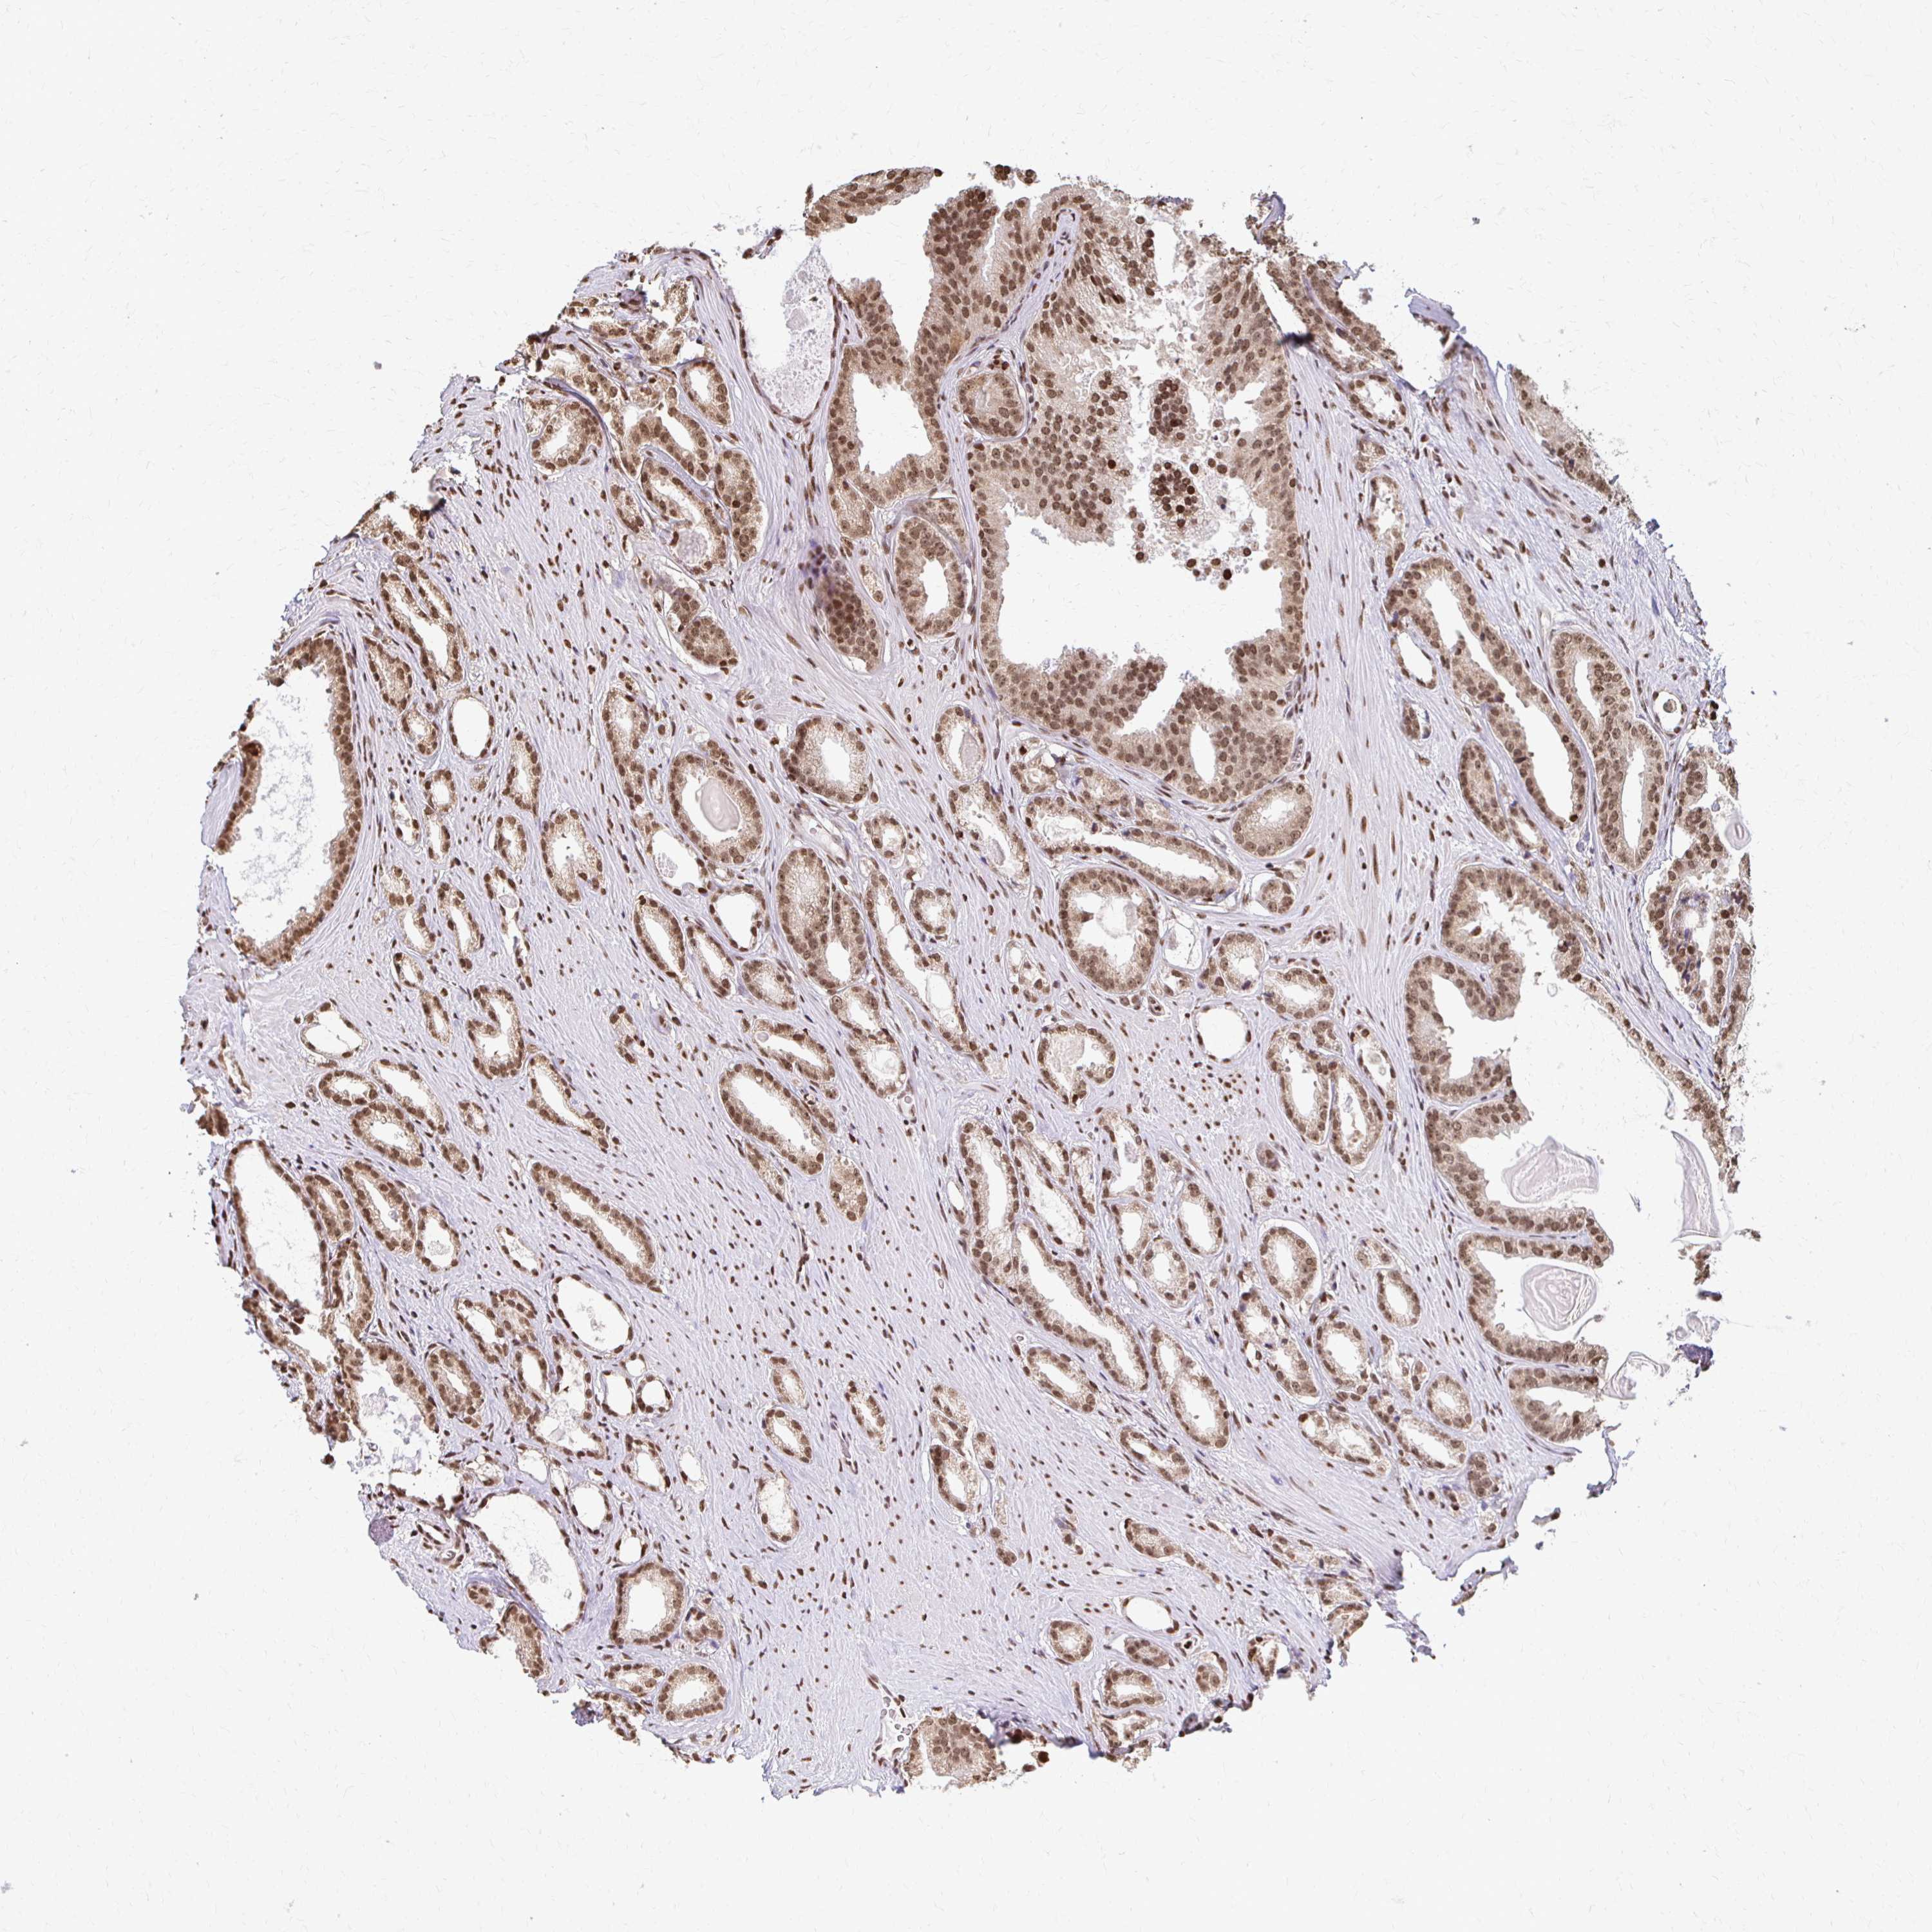

PROSTATE CANCER - Protein expressioni

A mouse-over function shows sample information and annotation data. Click on an image to view it in a full screen mode. Samples can be filtered based on level of antibody staining by selecting one or several of the following categories: high, medium, low and not detected. The assay and annotation is described here.

Note that samples used for immunohistochemistry by the Human Protein Atlas do not correspond to samples in the TCGA dataset.

Antibody stainingi

Antibody staining in the annotated cell types in the current human tissue is reported as not detected, low, medium, or high, based on conventional immunohistochemistry profiling in selected tissues. This score is based on the combination of the staining intensity and fraction of stained cells.

Each image is clickable and will lead to virtual microscopy that enables deeper exploration of all samples and also displays staining intensity scores, fraction scores and subcellular localization as well as patient and tissue information for each sample.

Antibody HPA061982

Staining

High

Medium

Low

Not detected

Intensity

Strong

Moderate

Weak

Negative

Quantity

>75%

75%-25%

<25%

None

Location

Nuclear

Cytoplasmic/membranous

Cytoplasmic/membranous,nuclear

Adenocarcinoma, High grade

Adenocarcinoma, Medium grade

Adenocarcinoma, Low grade